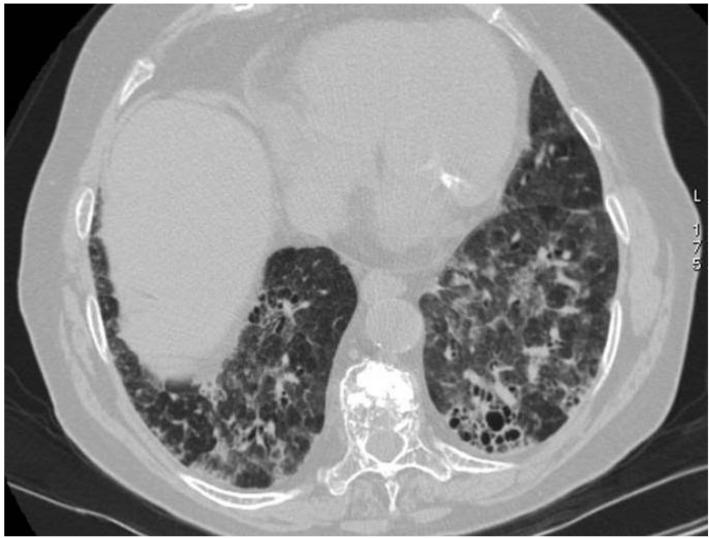

Vasculitides represent a heterogeneous group of immune-mediated disorders, characterized by a systemic inflammatory destructive process of the blood vessels resulting either in ischemia or hemorrhage. The organ involved and vessel size influence the pattern of presentation of the pathology. The lung is commonly involved in systemic vasculitides, with heterogeneous clinical, radiological, and histopathological presentations. Primary vasculitides most commonly associated with lung parenchymal involvement include small-vessel antineutrophil cytoplasmic autoantibody (ANCA)-associated vasculitides, such as granulomatosis with polyangiitis (GPA), eosinophilic granulomatosis with polyangiitis (EGPA), and microscopic polyangiitis (MPA). Several studies have reported cases of interstitial lung diseases (ILDs) associated with systemic vasculitis, particularly those positive for ANCA associated vasculitis/vasculitidis: AAV. We have selected from our case series different radiological features of pulmonary vasculitis (i.e., solitary or multiple nodules, cavitary lesions, nodules with centrilobular or peribronchial distribution, airspace consolidations, "crazy paving" appearance, interstitial disease), including cases with interstitial lung alterations. Therefore, the aim of this review is to describe the typical clinical manifestations of vasculitides and their main radiologic features (especially AAV).

血管炎是一组异质性的免疫介导性疾病,其特征是血管的系统性炎症性破坏过程,可导致缺血或出血。受累器官和血管大小会影响病理表现形式。肺部在系统性血管炎中常受累,临床表现、影像学表现和组织病理学表现各异。最常与肺实质受累相关的原发性血管炎包括小血管抗中性粒细胞胞浆自身抗体(ANCA)相关血管炎,如肉芽肿性多血管炎(GPA)、嗜酸性肉芽肿性多血管炎(EGPA)和显微镜下多血管炎(MPA)。多项研究报告了与系统性血管炎相关的间质性肺疾病(ILD)病例,尤其是那些ANCA相关血管炎/血管炎阳性的病例:AAV。我们从病例系列中选取了肺血管炎的不同放射学特征(即孤立或多发结节、空洞性病变、具有小叶中心或支气管周围分布的结节、气腔实变、“铺路石样”表现、间质性疾病),包括伴有间质性肺改变的病例。因此,本综述的目的是描述血管炎的典型临床表现及其主要放射学特征(尤其是AAV)。